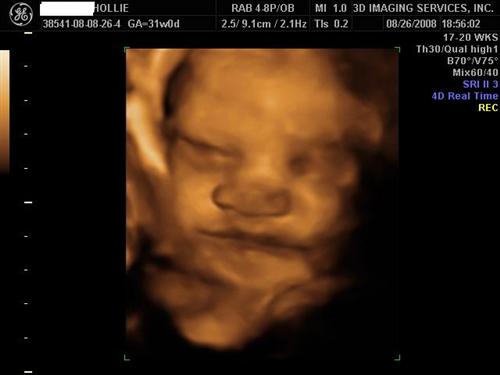

Girls who had 3D/4D sonos, please post...

Just curious to see some pics. My DH is getting me a 3D/4D package from Impact for my bday and I'm not sure when I want to go. I'm 25 weeks now so I definitely have to wait, but I'm not sure when the best time to go would be.

Please post your pics and how many weeks you were when you went. Thanx!